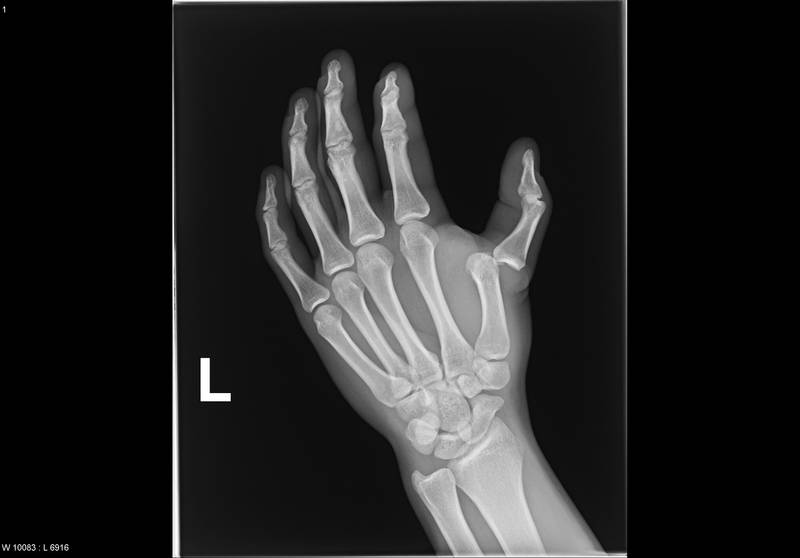

Самостоятельно практически невозможно дифференцировать вывих пальца руки от перелома. В обоих случаях имеет место хорошо заметное изменение внешнего вида конечности. Уточнить, имеется ли нарушение целостности костной ткани, можно только в ходе рентгенологического исследования.

Непосредственно в травмпункте врач собирает анамнез, т. е. проводит опрос и осматривает травмированную руку. Затем для уточнения характера повреждения направляет на рентгенографию. Если есть основания предполагать ущемление сухожилия, прибегают к дополнительным методам аппаратной диагностики – компьютерной или магнитно-резонансной томографии.